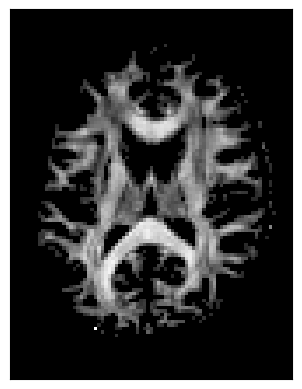

We can also compute the colored FA or RGB-map. First, FA needs tob e scaled between 0 and 1, then the RGB map can be computed and visualized.

FA = np.clip(FA, 0, 1)

RGB = color_fa(FA, tenfit.evecs)

plt.figure(figsize=(6, 6))

plt.imshow(np.rot90(RGB[:, :, sli, :], k=1)) # k=1 → 90° counterclockwise

plt.axis('off');

../_images/4b3ba26e8d2863f2234727760e057ee24f4711b11c7d3959dbc16a1ff75ff1ea.png